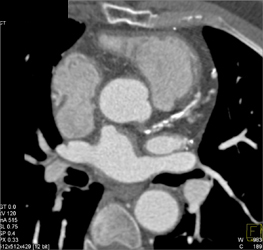

Internal Mammary Artery-look Good